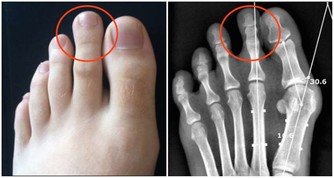

第三個信號:指甲出現豎紋、小白塊,月牙少指甲的這些特徵是說明你的身體缺乏鋅、維生素A、B等元素,

但這些身體必不可少的微量元素也是身體擁有一個好免疫力的關鍵。

所以如果你指甲上的月牙越少、小白點/白塊越多,都說明是你的疾病抵抗力在降低的表現。

第四個信號:更容易傳染疾病,傷口更難癒合免疫力降低,我們的身體也就更容易被疾病傳染,同時清除外來病菌的能力也會更弱。

所以這就會導致傷口需要更久的時間癒合,一些皮膚疾病也更難根治。

如灰指甲和甲溝炎等皮膚疾病反反覆復,就有受到身體的免疫力降低的影響因素。